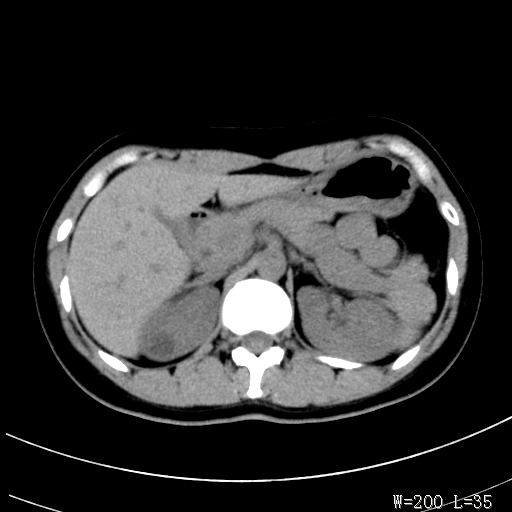

标题: CT25345:右肾占位。 [打印本页]

标题: CT25345:右肾占位。

女,30岁,右腰部胀痛3个月。

增强无明显强化,先考虑血管平滑肌脂肪瘤,建议作薄层扫描右mri检查,

感觉像囊肿.

囊肿!

考虑右肾近上极囊肿;建议必时行mri检查。